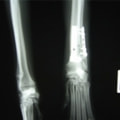

ペルシャ猫 11ヶ月齢 雄

他院にて左大腿骨遠位の成長板骨折(salter-harrisⅠ型)が認められており、治療相談を目的として来院。当院にて、キルシュナーワイヤーを用いたピンニングにより骨折部位の整復を行いました。術後の経過は良好で、現在も経過観察中です。

術後レントゲン